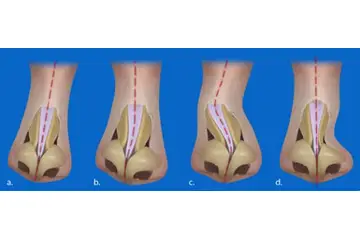

Diz Kıkırdak Hasarının Tanısı Diz kıkırdak hasarının tanısı, genellikle bir ortopedi uzmanı tarafından konulur. Tanı sürecinde şu yöntemler kullanılabilir:

Diz Kıkırdak Hasarının Tedavi Yöntemleri Diz kıkırdak hasarının tedavisi, hasarın ciddiyetine ve bireyin genel sağlık durumuna bağlı olarak değişir. Tedavi yöntemleri arasında şunlar bulunmaktadır: